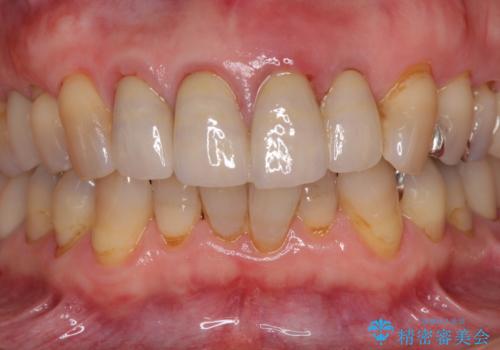

3. 折れてしまった前歯 インプラントによる補綴治療の治療後